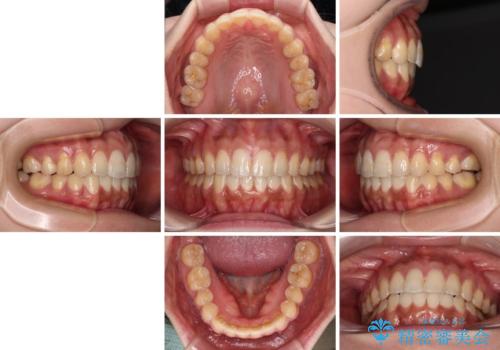

舌のトレーニングをしっかりと行っていただき、上下前歯をしっかりと接触させることができました。

咬合力が強いため、治療途中に奥歯が咬み合わない期間が続きましたが、上下の奥歯でゴムかけを行っていただき、違和感なく咬み合うように仕上げることができました。